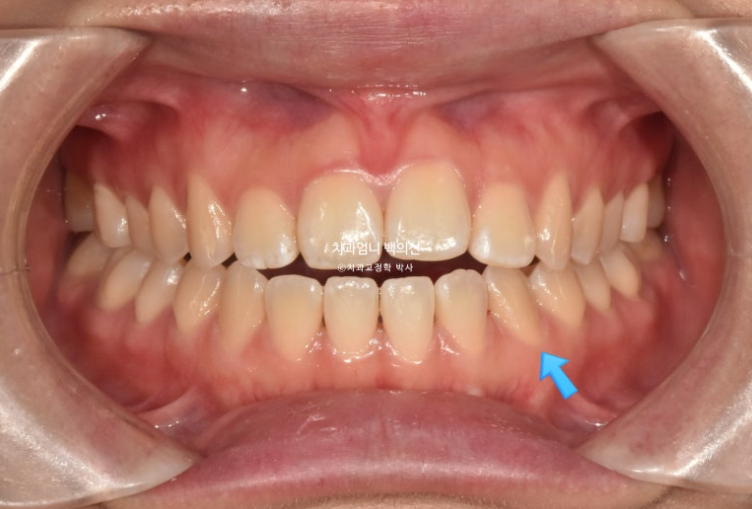

파란 화살표 송곳니는 안쪽으로 쓰러져 있습니다.

파란 화살표 접착제가 까맣게 보이는 것은 접착제가 치아와 분리된 상태이기 때문입니다.

24.12

사용한 부분교정용 장치는 MTA 미니튜브 이고 고무줄 처방이 함께 들어갔습니다.

윗니가 아랫니를 앞에서 안정적으로 덮게 만들려면 아래 앞니에 치간삭제가 소량 필요합니다.